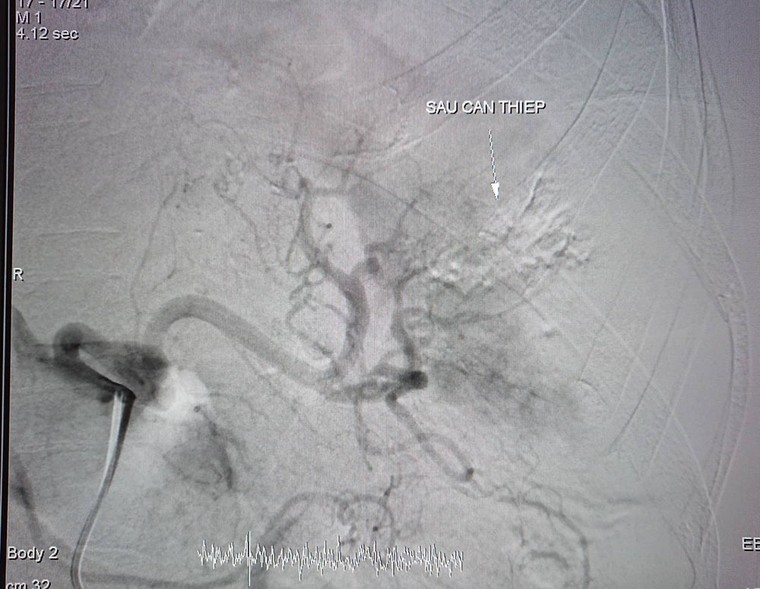

Sau khi đặt coil, bác sĩ tiến hành chụp kiểm tra và cho kết quả đã bít hoàn toàn lỗ dò động tĩnh mạch và đoạn giả phình mạch.

Thời gian thực hiện thủ thuật là 30 phút. Bệnh nhân không cần phẫu thuật mổ mở thận để cắt giả phình mạch.

Đến hôm nay, bệnh nhân tỉnh, tiếp xúc tốt, hết tiểu máu, dự kiến ngày mai sẽ xuất viện.